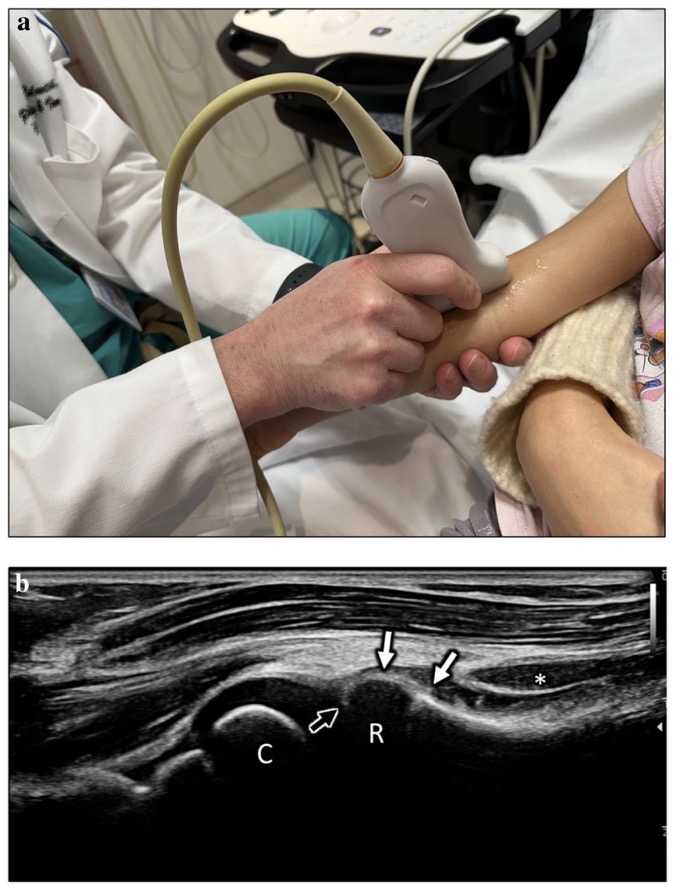

Technique:

approche antérieure dans un axe long à l'articulation radiocapitellaire.

=> Tête radiale non ossifiée (R)

Capitillum partiellement ossifié (C)

Muscle supinateur (*)

Ligament annulaire (flèches blanches)

Pli synovial antérieur (flèche noire)